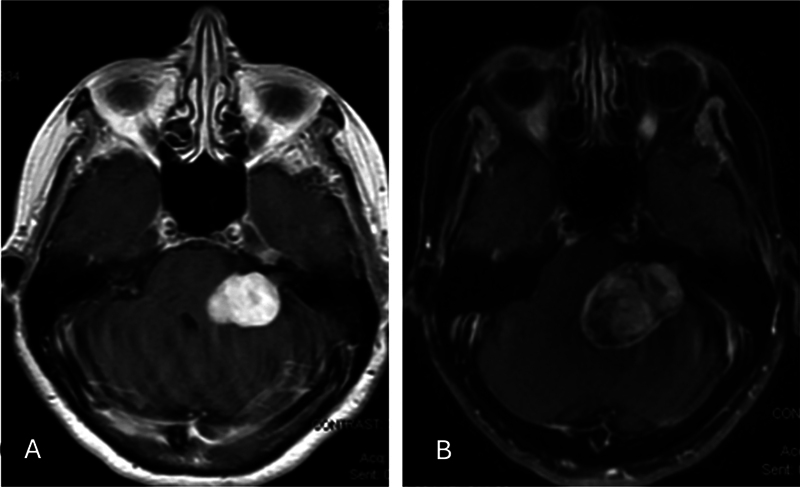

Case presentation: A 75-year-old female presented to the hospital with a 1-month history of left-sided facial numbness, loss of taste on the left side of her tongue, severe dysarthria, and recent-onset cranial nerve VI and VII palsies. MRI of the brain with and without contrast demonstrated an enlarging cerebellopontine angle mass and signs of brainstem compression. The patient underwent a left retrosigmoid craniotomy and surgical resection. Pathology and immunohistochemistry sequencing findings were consistent for MPNST with rhabdomyoblastic differentiation (malignant triton tumor). An outside review of the case by a large academic institution concurred with the diagnosis. The patient did not report any previous history of irradiation.